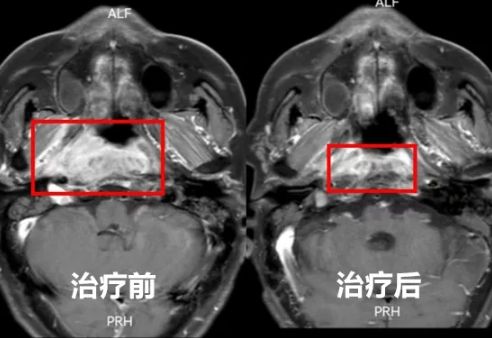

经过几个月的规范治疗,刘先生的病情终于得到了控制。复查结果显示,肿瘤明显缩小,各项指标也逐渐恢复正常。这个消息让刘先生和他的家人欣喜若狂,终于看到了胜利的曙光。